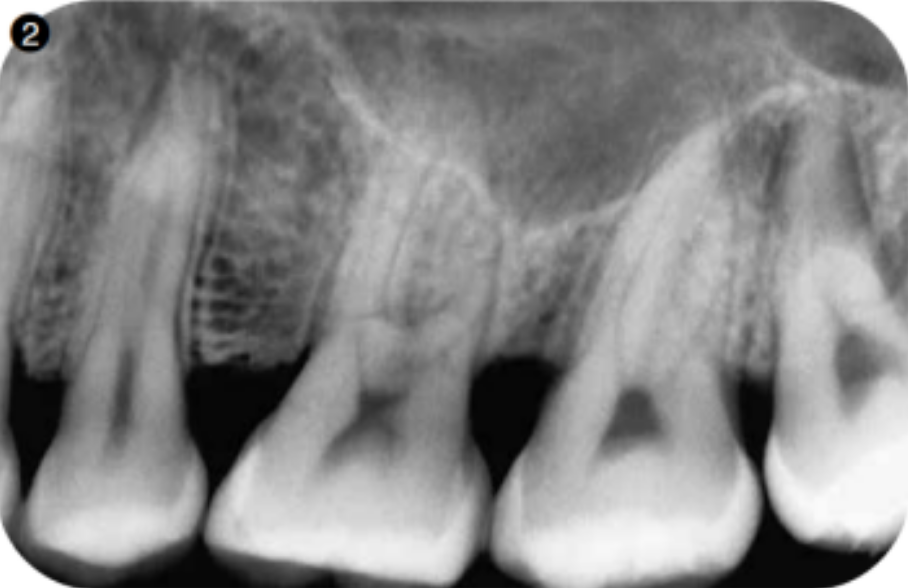

在牙片上确认有无牙周膜间隙及骨白线图2。即使看上去像是根尖突出在上颌窦内,但如果可以看到这些结构的话,根尖部就有菲薄的骨,因此只要不向根尖方向施加过大的压力,轻柔拔牙的话,并不一定会穿孔。

图2 可以看到26的腭侧根从上颌实底向窦内突出。这种牙在变成残根后,在拔牙时要注意避免穿孔